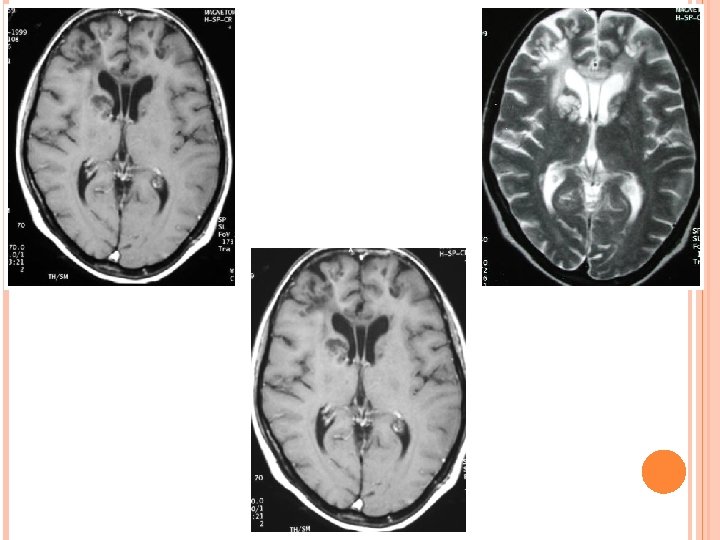

Depending on its stage of maturation tuberculoma’s appearance varies on MRI. Stages of tuberculoma: Non caseating Caseating with solid centre Caseating with liquid centre

NON CASEATING Hyperintense on. T 2 W images and slightly hypointense on T 1 W images with homogeneous post contrast enhancement.

CASEATING WITH SOLID CENTRE: Hypo to isointense on both T 1 W and T 2 W images with an iso to hyperintense rim on T 2 W images. In presence of an edema rim is inseparable on T 2 W images. Shows rim enhancement on post contrast T 1 W images.

CASEATING WITH LIQUID CENTRE: When the solid centre liquefies it appears hyperintense on T 2 W images with surrounding hypointensity. On post contrast images show rim enhancement.